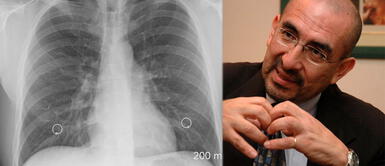

Asimismo, el experto en salud pública mencionó que cuando una personas tiene signos de COVID-19 sí es de gran ayuda la ecografía pulmonar.

"Pero, si es un paciente con historia de haber estado expuesto, de repente si tiene síntomas, un poco de tos o falta de aire al subir las escaleras, allí sí ayudaría una ecografía o la radiografía", remarcó el médico epidemiólogo Huerta.